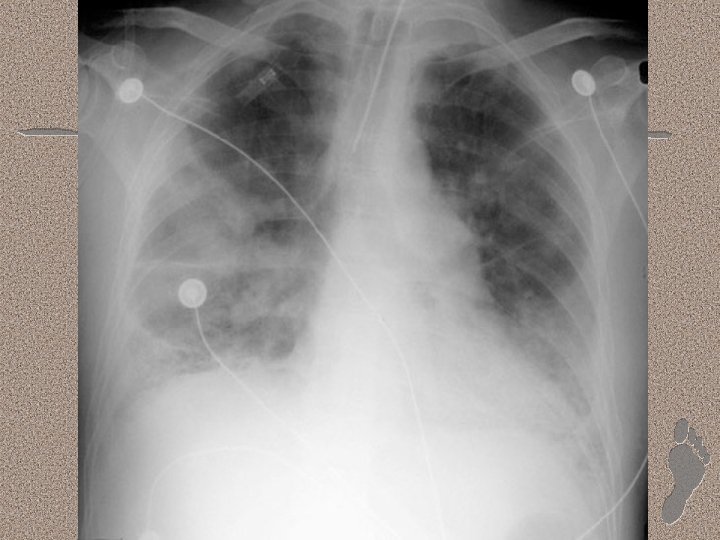

Pemeriksaan Penunjang • Laboratorium • AGD : alkalosis respiratorik pada fase awal, dan berganti menjadi asidosis respiratorik pada fase lanjut • Leukositosis (sepsis), anemia, trombositopenia (SIRS), peningkatan kadar amilase (pankreatitis) • Gangguan fungsi ginjal dan hati. • Pencitraan • • Foto dada : gambaran radioopak difus CT-Scan : pola heterogen, predominasi infiltrat pada dorsal paru (supine)